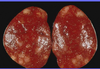

Salmonella Pullorum

Nekrose i myocardium, lyse områder